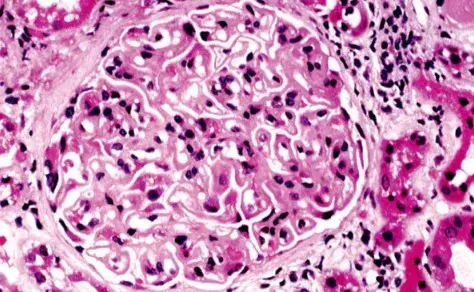

Nefropatia Membranosa: e se o paciente não responder ao tratamento inicial?

Nefropatia Membranosa: e se o paciente não responder ao tratamento inicial?

Neste vídeo, abordamos estratégias para lidar com pacientes com nefropatia membranosa que não respondem ao tratamento inicial. Ele enfatiza a importância da reavaliação constante e do ajuste do regime de tratamento com base nos resultados e no estado do paciente.

Como fazer o tratamento da Nefropatia Membranosa de forma prática!

Como fazer o tratamento da Nefropatia Membranosa de forma prática!